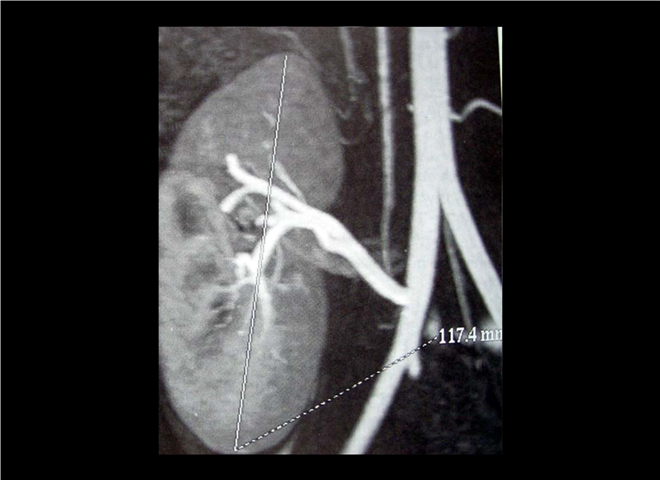

13_CT增强扫描